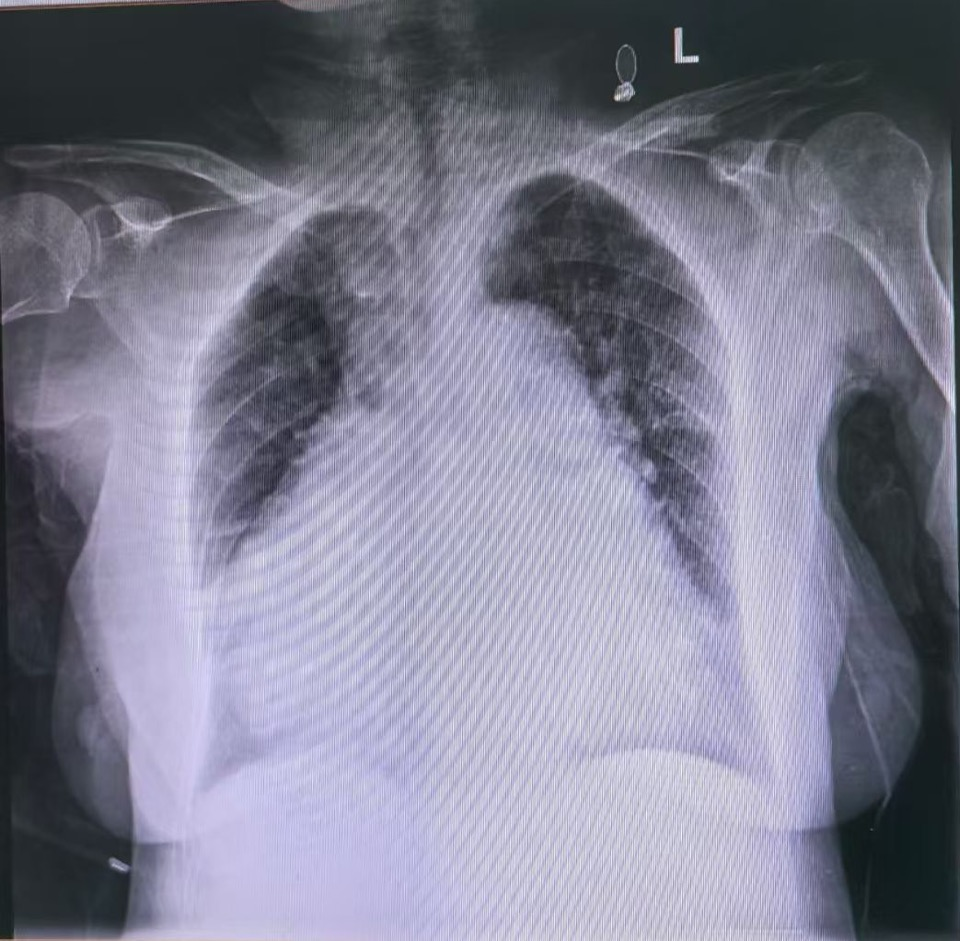

许奶奶胸片检查:心脏扩大

83岁的许奶奶,因反复胸闷、心悸7年余,再发伴头晕、乏力半月余入我院治疗。既往有冠心病、高血压病、心房纤颤病史10余年,长期服用药物治疗。考虑到患者年龄大,消瘦,长期服用抗凝药物,心内一科李顺辉主任带领电生理团队缜密分析、认真讨论,一致认为植入新型可回收式无导线心脏起搏器更适合许奶奶身体状况。

因传统起搏器植入术后伤口愈合难,感染风险高,且长期影响三尖瓣的开合,导致三尖瓣的返流,而螺旋固定式无导线起搏器术中,无导线装置在未旋入情况下多次无创伤测试,以选择最佳起搏位点,减少心肌损伤、且术后电池寿命长,可减少更换次数,可取出且未来可升级为真双腔,降低三尖瓣返流风险。综合考虑预后及患者家属意愿,经仔细评估、充分沟通决定,为许奶奶开展螺旋主动固定式无导线心脏起搏器植入术